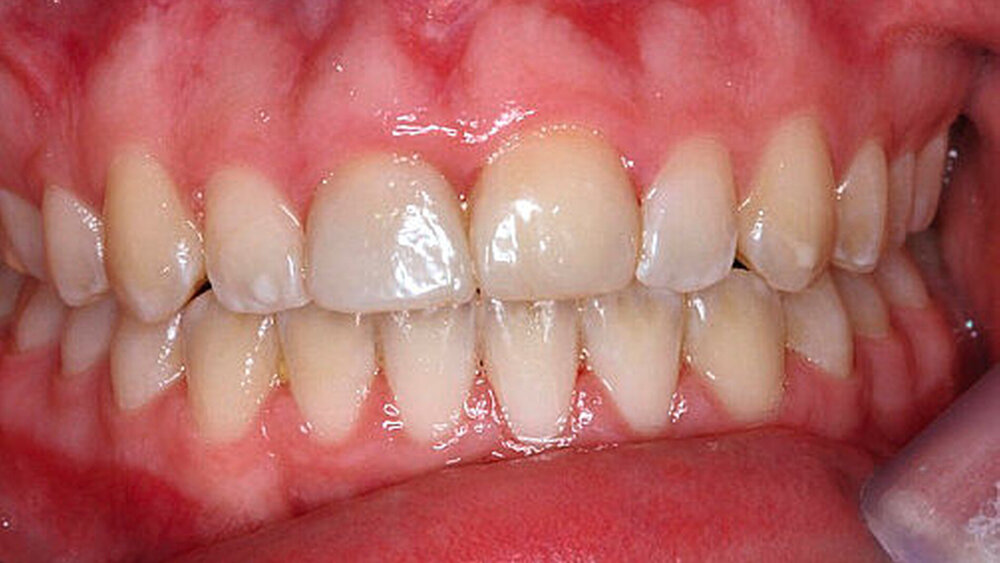

Die dargestellten Behandlungsempfehlungen sollen nun – zuerst am klinischen Fall eines elfjährigen Mädchens – reflektiert werden (Abbildung 3): Die anamnestische Angabe einer Trockenlagerungszeit des avulsierten Zahnes von rund 60 Minuten muss als extrem ungünstig für die Langzeitprognose des Zahnes angesehen werden. Die Replantation des Zahnes durch den Hauszahnarzt war trotz dieser Lagerungsbedingungen völlig richtig. Lediglich die nach folgende Therapie (Schienungsart: rigide; Schienungszeit: zwei Jahre; keine weiteren Röntgenkontrollen und damit auch keine Wurzelkanalbehandlung nach ersten Anzeichen einer Wurzelresorption) entspricht nicht den Anforderungen an eine adäquate posttraumatische Nachsorge. Daraus ergeben sich sekundäre Probleme für das weitere Kieferwachstum (posttraumatische Ankylose), die im Folgenden besprochen werden.

Umgang mit primären und sekundären Verlusten: Die Therapie der posttraumatischen Ankylose im jugendlichen Gebiss stellt eine der schwierigsten therapeutischen Aufgaben dar. Mittelfristig kommt es zum vorhersagbaren Zahnverlust bedingt durch fortschreitende Wurzelresorption (sekundärer Verlust).

Abbildung 4a stellt einen weiteren Fall einer posttraumatischen Ankylose nach Avulsion und Replantation des Zahnes 11 mit rund 60-minütiger Trockenlagerungszeit bei einem zwölfjährigen Jungen vor, bei dem es inzwischen (pubertärer Wachstumsschub) zu einem erheblichen vertikalen Wachstumsdefizit des betroffenen Kieferabschnitts in regio 11 gekommen ist: Das Weichteildefizit im Vergleich zum gesunden Nachbarzahn beträgt etwa 3 mm. Es zeichnet sich bereits ab, dass eine spätere implantologische Versorgung des Patienten im Alter von etwa 18 Jahren nur mit hohem chirurgischem Aufwand möglich sein wird.